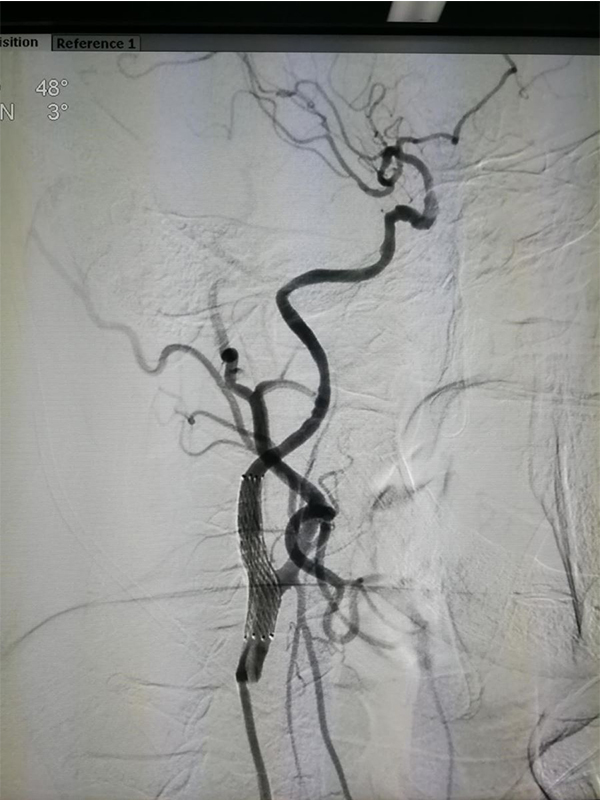

MRA CTA (CT ) DSA <50 %) MRA 50 % CTA 80% DSA 99 % ( ) CTA DSA

CTA 100 % 63 %(95 % 25 %-88 %) 70 % 100 %